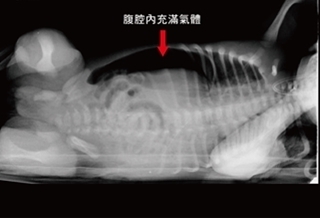

(優活健康網記者張桂榕/綜合報導)3天以上不解大便、不放屁、腹脹、腹痛就要注意了!31歲年輕男子,因腹脹不舒服求診,經腹部X光發現他不但是「先天性乙狀結腸過長」,無扭結但形成交叉壓迫腸道,使整條乙狀結腸因糞便積留脹成宛若「車輪」似的。澄清醫院中港院區大腸直腸外科主治醫師馬秀峰表示,經以肛管由肛門進入約20公分處,將被壓扁窄化的腸道撐開,剎那間排出腸道內的氣體及糞便,患者立即解決腹脹的困擾。同時強調,先天乙狀結腸過長的人,年輕時比較不會造成扭結的現象,但很容易復發,隨著年紀增大越有扭結的風險,將來年紀增大因大腸蠕動減緩,容易導致過長的乙狀結腸扭結,如果錯失治療時機,恐會導致扭結的腸道缺血而變黑壞死,引起腹膜炎而危及生命,最好及早做縮短手術以免後患。乙狀結腸過長難自覺 但有跡可尋正常的大腸系統像ㄇ字形,乙狀結腸位於降結腸和直腸之間,人體的腸子都有一定比例的長度,正常的長度在20公分到30公分之間,乙狀結腸是屬於游離的腸道,如果因先天乙狀結腸過長,因其有游離性就容易扭結,造成腸子鎖死,會因缺血壞死,使整條腸子變黑。先天乙狀結腸過長的長度約在50公分至60公分之間。腹脹、腹痛、便秘、不解便、不放屁 要注意該患者接受乙狀結腸縮短手術,切除約40公分的乙狀結腸,接上降結腸和直腸,讓整個大腸腸道恢復正常狀態。馬秀峰醫師說,先天性乙狀結腸過長,基本上不會有任何症狀,因過長的長度不一,也會導致不同的結果,如果超過50公分再加上高齡或臥病,發生乙狀結腸扭結的風險就高,因此如因腹脹、腹痛、便秘而發現是先天性乙狀結腸過長造成的疾病,建議及早做縮短乙狀結腸手術,以免一再復發甚至危及生命的後果。